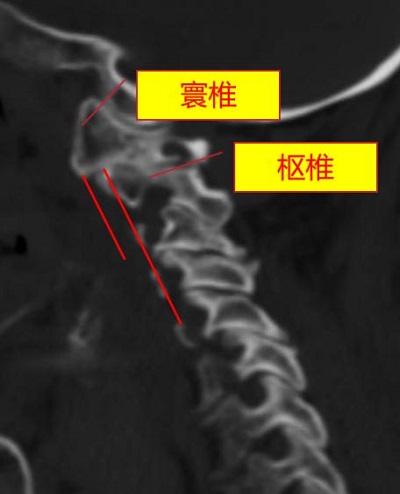

術前,頸椎MRI顯示,患者脊髓嚴重受壓(圓圈處)。重慶市人民醫院(重慶大學附屬人民醫院)供圖